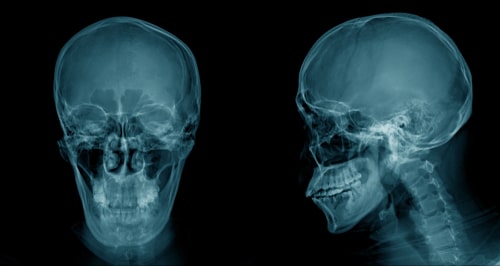

Any serious bodily injury has the potential to impact a person’s quality of life, but the implications of a brain injury are often especially severe. A traumatic brain injury (TBI) occurs when the head is struck with a force that causes the brain to bruise, bleed, or suffer damage.

- Penetrating Injury: An object literally fractures the skull and penetrates the brain. A gunshot to the head is the most common example.